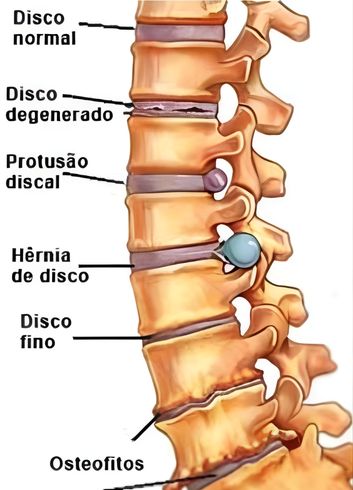

Ao ler o termo “doença degenerativa” em um laudo de ressonância magnética, é comum que o paciente sinta medo, imaginando uma condição grave e progressiva. No entanto, na grande maioria dos casos, a doença degenerativa do disco nada mais é do que o processo natural de envelhecimento da coluna vertebral. Assim como nossa pele ganha rugas e nossos cabelos ficam brancos, nossos discos intervertebrais também sofrem alterações com o passar dos anos, perdendo hidratação e altura.

Esse processo de desgaste começa silenciosamente. O disco, que funciona como um amortecedor entre as vértebras, começa a desidratar e a perder sua elasticidade. Isso pode levar a uma instabilidade na coluna ou diminuir o espaço por onde passam os nervos. Embora muitas pessoas com degeneração discal não sintam absolutamente nada, em alguns casos, esse desgaste pode evoluir para quadros de dor crônica, rigidez ou até facilitar o surgimento de hérnias de disco.